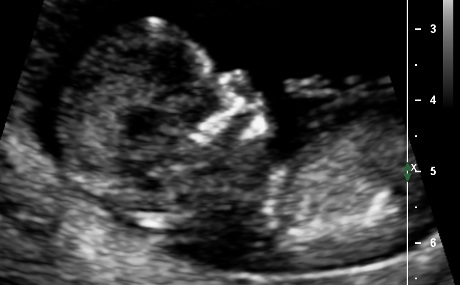

Well went for my scan today, baby was very photogenic! I was exactly 13 weeks.

Not sure what i feel, i am so in love with this baby already. Its funny coz even tho I swayed i am realy not bothered about gender, will not be finding out gender until birth but still would love guesses. Tech gave me her feeling what she thought.

Attachment 3732Attachment 3733Attachment 3734